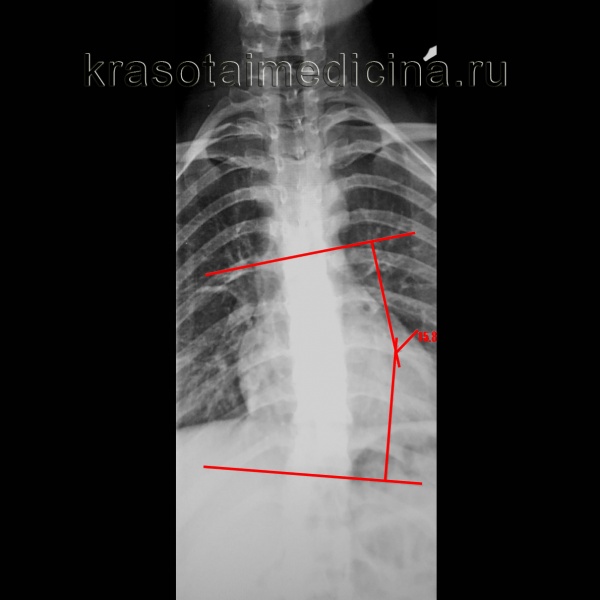

о Стандартным методом количественной оценки величины сколиотической деформации является метод Кобба:

- Строятся две линии, соответствующие замыкательным пластинками терминальных позвонков

- Если четко дифференцировать замыкательные пластинки не удается, в качестве ориентиров используют корни дуг

- Угол Кобба - это угол между замыкательными пластинками двух терминальных позвонков

- Можно измерять угол между двумя перпендикулярами к замыкательным пластинкам терминальных позвонков

- Этот второй метод упрощает измерение при небольших искривлениях

Рентгенография грудного отдела позвоночника. Левосторонний сколиоз 2-й ст. с углом дуги около 15,8 градусов (по Коббу), с центром на Th9.